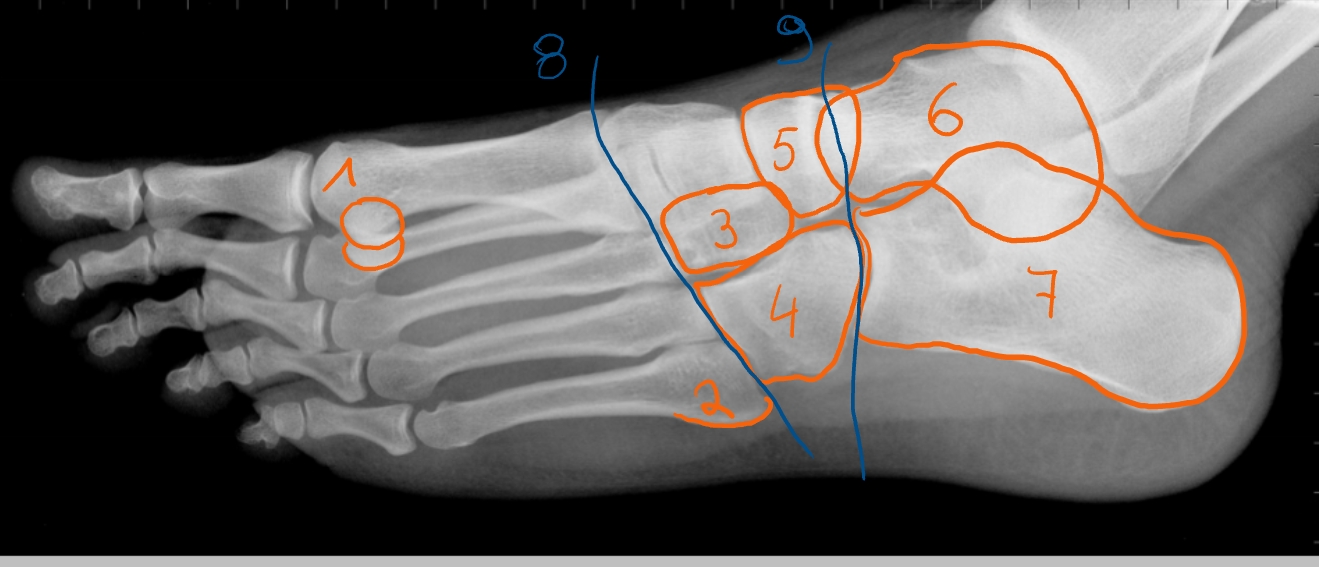

talus

collum tali

caput tali

os naviculare

calcaneus

tuber calcanei

Achillespees → van m. triceps surae

malleolus medialis

malleolus lateralis

→ linker enkel

tibia

talus

calcaneus

Achillespees

gewrichtslijn van Chopart

os naviculare

os cuboideum

ligamentum talo-fibulare anterius

wordt uigerokken/ gescheurd bij een verstuikte voet (als je je voet omslaat)

Achillespees

talus

fibula

os cuneiforme mediale

os cuboideum

os cuneiforme laterale

→ 1e foto: anteroposterieure foto (om de mediale cuneiforme te zien)

→ 2e foto: schuine foto (om de intermediale en laterale cuneiforme te zien)

hallux

2 sesambeentjes

os cuneiforme mediale

os naviculare

os cuboideum

gewrichtslijn van Chopart

2 sesambeentjes

tuberositas van metatarsaal 5

os cuneiforme laterale

os cuboideum

os naviculare

talus

calcaneus

gewrichtslijn van Lisfranc

gewrichtslijn van Chopart